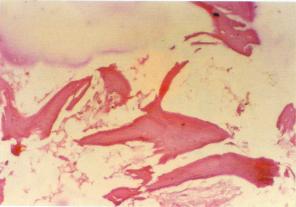

病理

病理分期肘關節結核休息、制動和營養:全身情況的好壞與肘關節結核病灶的好轉或惡化有密切關係。休息和營養作為改善全身情況的一個重要步驟是不可忽視的。休息使機體代謝降低,消耗減少,體溫下降,體重增加,有利於肘關節結核患者體力的恢復。局部制動使肘關節結核病變處負重減輕,活動減少,既能減少疼痛,又能防止肘關節結核病變擴散,有利於組織修復。